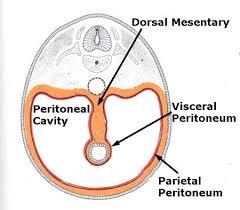

Serous membranes

...

2

Parietal Peritoneum

3

Dorsal Mesentery